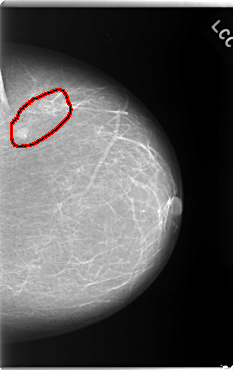

FILE: C_0132_1.LEFT_CC.OVERLAY

TOTAL_ABNORMALITIES 1

ABNORMALITY 1

LESION_TYPE CALCIFICATION TYPE PLEOMORPHIC DISTRIBUTION CLUSTERED

LESION_TYPE MASS SHAPE OVAL MARGINS CIRCUMSCRIBED

ASSESSMENT 4

SUBTLETY 5

PATHOLOGY MALIGNANT

TOTAL_OUTLINES 1

BOUNDARY